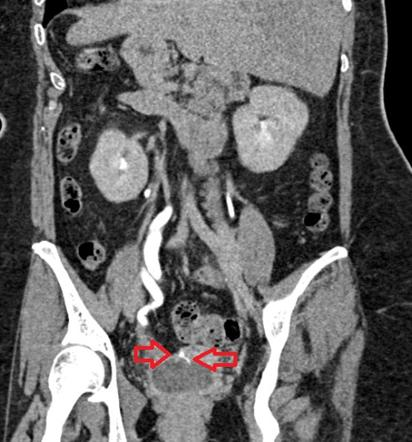

- CT KUB: if obstruction is suspected (to identify the site of obstruction

- CT KUB or IV pyelography or Cystoscopy or Retrograde pyelogram